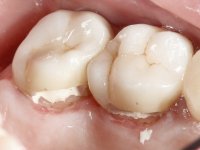

Teeth 17 and 16 were prepared for the fabrication of a 2-element Zr bridge. The impression was performed with a double mixing technique and a monolithic bridge in Zr was made in the laboratory. 4 years later, an abscess appeared in the apical area of tooth 26. It was decided to remove the bridge, remove the intra-radicular posts and retract the endodontic treatments of teeth 17 and 16. The removal of the bridge was carried out by making two cervical cavities. in the palatal area of the bridge and with a microluxator, disinsertion movements were performed. The intra-radicular posts were removed using fine drills and an ultrasound tip. The bridge was provisionally cemented and the patient was referred to a fellow endodontist for endodontic retreatment. After the retreatment, the intraradicular posts were placed again and the bridge was definitively cemented. One year later, a new abscess appears, possibly related to a root fracture. The bridge was sectioned between tooth 27 and 26 and tooth 26 was extracted and the crown of 27 was provisionally cemented. 3 months later, teeth 27 and 25 were prepared and a temporary bridge was made in dual polymerization resin. Then, an impression was made using the double mixing technique and a 3-element bridge in Zr was made in the laboratory. It was permanently cemented in the mouth with resin-reinforced glass ionomer cement.